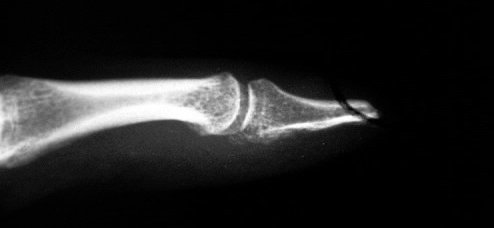

In the amputation revision as a DIP disarticulation, the palmar digital nerves are buried in drill holes the head of the proximal phalanx to avoid sensitive neuroma symptoms.

Drill holes in the bone with protected intraosseous neuroma.